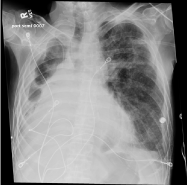

Due to its association with H. capsulatum, most patients usually have a diagnosis via serological assay or bronchioalveolar lavage [11,18]. Definitive diagnosis for histoplasmosis has been achieved via antibody titers or Grocott methenamine silver stains revealing H. capsulatum [11]. There is no definitive laboratory assay to diagnose FM. Due to its host immune modulated response, some genetic markers related to human leukocyte antigen markers has been identified, however more definitive studies are lacking [19]. Chest radiographs (Figure 2) can assist in diagnosis, usually showing enlarged perihilar and mediastinal lymph nodes. It is important to note that some chest radiographic findings are non-specific, including widening of the mediastinum, cavitary lesions, and adenopathy, prompting further workup with chest Computerized Tomography (CT) and/or bronchoscopy [8] (Figure 3 and Figure 4). Chest CT usually shows focal or diffuse fibrosis, usually confined to the middle mediastinum [20]. The focal appearance of the fibrosis appears more frequently in cases of FM than the diffuse pattern. Rarely is the posterior mediastinum involved [21]. As with most cases of FM, contrast enhanced imaging will depend on the structures involved. If vasculature is involved, contrast enhanced CT will benefit in confirming the diagnosis (Figure 5 and Figure 6). Other modalities, including MRI, esophagram or contrast pulmonary arteriogram may be useful to rule out malignancy or other mass effect causing lesions. It is important to note that the other modalities are not as efficient in representing the degree of calcification and fibrosis, therefore CT imaging should be the modality of choice if FM is suspected [8,20,22].

Figure 3: Disease progression seen on PA chest X-ray with tracheal deviation. View Figure 3